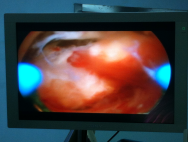

诊疗过程:入院后完善相关辅助检查,予以在腰麻下行宫腔镜电切术:患者取膀胱截石位于手术台上,腰麻成功后,碘伏常规消毒会阴部手术野皮肤及阴道,妇科检查:外阴已产式,阴道畅,分泌物少,无异味,宫颈轻度糜烂,无举痛。子宫常大,无压痛。双附件未及明显异常。探宫腔225px,用20%甘露醇作膨宫液行宫腔镜检查术,宫腔形态规则,宫腔内右后壁近输卵管开口处见4.0*2.5*50px胎盘机化绒毛样肿物突起,内膜少,两输卵管开口清晰可见,宫颈管形态正常,用环形电极行电切术,术中见深达肌层。符合“胎盘植入”。充分止血后。检查宫腔形态正常。术毕。切除物送病理检查:坏死组织中有少许子宫内膜及钙化、机化组织。